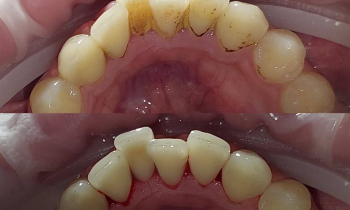

Наш ортодонт Евгений Владиславович Алексеев использует в своей работе не только стандартные общепринятые методики, но и самые современные, такие как аппарат Марко Роса